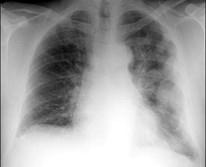

男,52岁,胸痛、体重下降,请结合胸片选出最可能的诊断()A.包裹性胸腔积液B.胸膜肥厚C.化脓性胸膜炎D.肺癌E.胸膜间皮瘤

问题 男,52岁,胸痛、体重下降,请结合胸片选出最可能的诊断()

选项 A.包裹性胸腔积液 B.胸膜肥厚 C.化脓性胸膜炎 D.肺癌 E.胸膜间皮瘤

答案 E